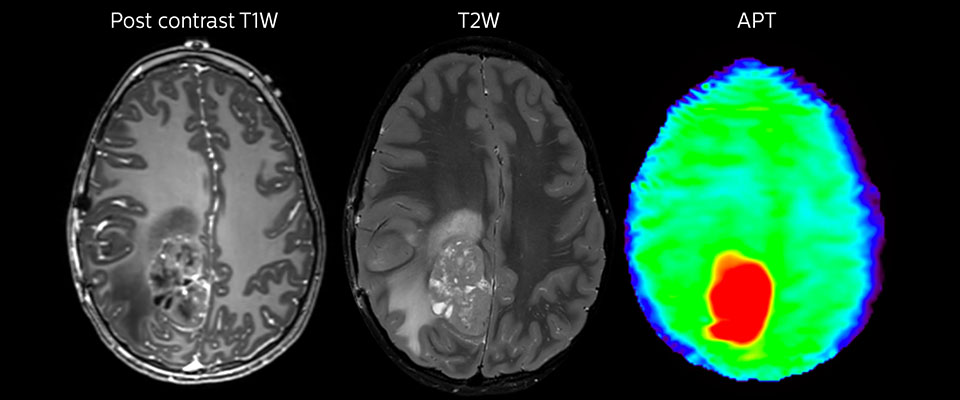

Grosse metastatische Hirnläsion

Diese 10-jährige Patientin unterzog sich vor 7 Jahren der Resektion eines Ewing-Sarkoms, doch jetzt wurde eine grosse metastatische Läsion im Gehirn entdeckt. Diese Läsion zeigt deutlich ein erhöhtes APT-Signal.

Eine MRT kann nach der Tumorresektion erfolgen, um auf Residualtumorgewebe oder erneutes Tumorwachstum zu untersuchen. Auch hier können die verschiedenen Kontrastmechanismen von APT die Diagnose unterstützen. Dr. Miller erinnert sich an einen bestimmten Fall. „Nach einer sehr guten Resektion sahen wir kleine Veränderungen auf den kontrastverstärkten T1-gewichteten und T2-gewichteten Bildern, die wie eine geringe Menge postoperativer Flüssigkeit aussahen. Interessanterweise sahen wir jedoch auch einen fokalen Bereich mit einem APT-Signal direkt in der Mitte der Anomalie. Wie immer, wenn wir ein wenig unsicher sind, führten wir weitere Untersuchungen durch und fanden leider neues Tumorwachstum in dieser Region“, so Dr. Miller. „Fälle wie dieser motivieren mich und andere, die sich um dieses Patientenklientel kümmern, zu untersuchen, wie dieses APT-Verfahren auf hohem Niveau für diese Patienten genutzt werden könnte und uns hilft, hochwertige diagnostische Informationen zu erhalten.“ Die Ärzte des Krankenhauses hatten auch einen Fall, in dem APT negativen Vorhersagewert hatte. Nach der Resektion eines hoch differenzierten Tumors gab es eine ähnliche geringfügige Veränderung auf den Bildern dieses Patienten. In diesem Fall war das APT-Signal jedoch ziemlich niedrig. In einem kürzlich durchgeführten Scan des Patienten wurde kein Rezidiv festgestellt.